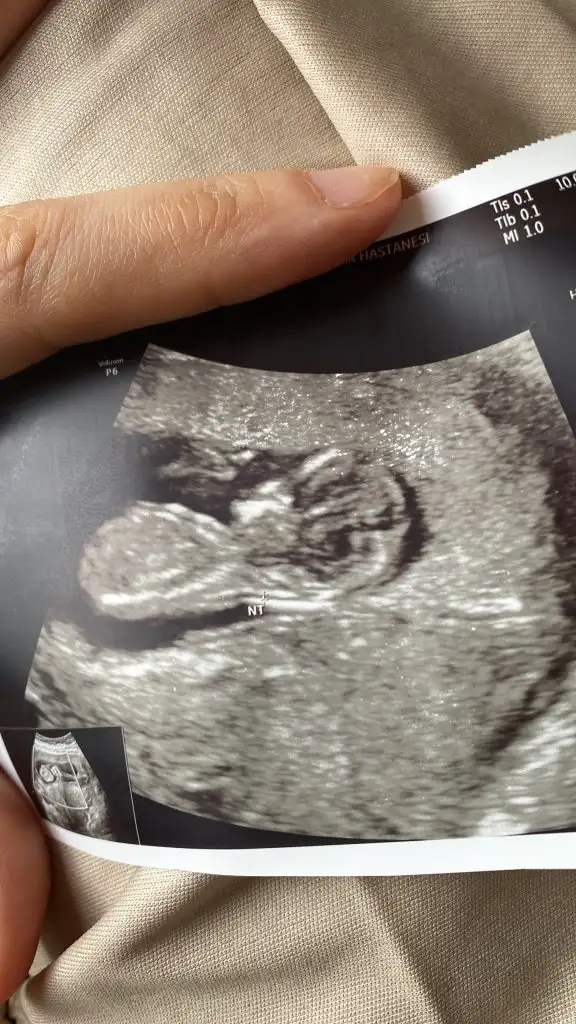

Rica etsem banada bakarmisiniz çok merak ediyorum 🥰☺️❤️

Eklentiler

• Screenshot_20230204-002246.webp

Screenshot_20230204-002246.webp

13,7 KB · Görüntüleme: 92

• IMG_20230202_182730_387.webp

IMG_20230202_182730_387.webp

23,3 KB · Görüntüleme: 67

• IMG_20230202_182706_519.webp

IMG_20230202_182706_519.webp

25 KB · Görüntüleme: 77

• IMG_20230202_182701_639.webp

IMG_20230202_182701_639.webp

27 KB · Görüntüleme: 83